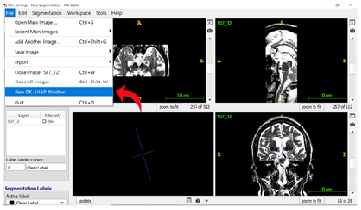

Step 2: Opening the T1 Image Select “File” from the top ribbon again, then click “New ITK-Snap Window” to open the T1-weighted image for the same subject.